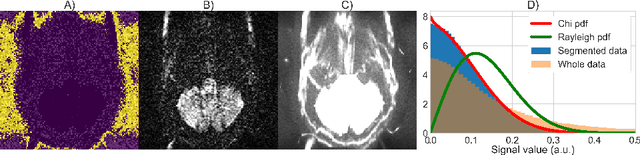

Abstract:Knowledge of the noise distribution in magnitude diffusion MRI images is the centerpiece to quantify uncertainties arising from the acquisition process. The use of parallel imaging methods, the number of receiver coils and imaging filters applied by the scanner, amongst other factors, dictate the resulting signal distribution. Accurate estimation beyond textbook Rician or noncentral chi distributions often requires information about the acquisition process (e.g. coils sensitivity maps or reconstruction coefficients), which is not usually available. We introduce a new method where a change of variable naturally gives rise to a particular form of the gamma distribution for background signals. The first moments and maximum likelihood estimators of this gamma distribution explicitly depend on the number of coils, making it possible to estimate all unknown parameters using only the magnitude data. A rejection step is used to make the method automatic and robust to artifacts. Experiments on synthetic datasets show that the proposed method can reliably estimate both the degrees of freedom and the standard deviation. The worst case errors range from below 2% (spatially uniform noise) to approximately 10% (spatially variable noise). Repeated acquisitions of in vivo datasets show that the estimated parameters are stable and have lower variances than compared methods.